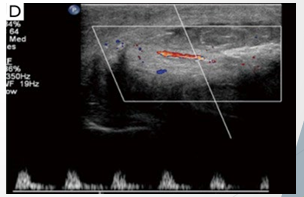

Patient attempting to urinate whilst penis erect. Heard ‘crack’ followed by acute pain

Normal arterial flow noted in left cavernosal artery. Important to rule out vascular injury